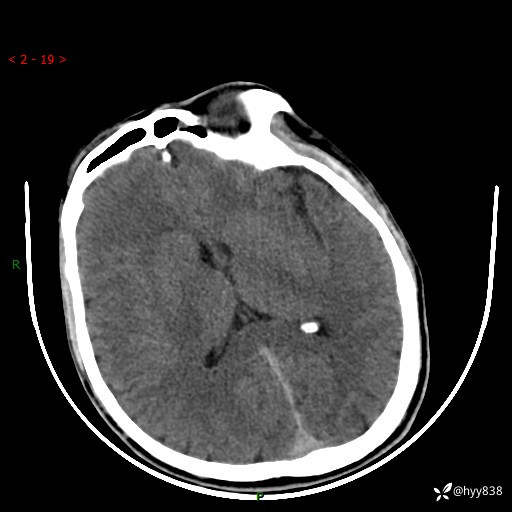

颅脑CT平扫